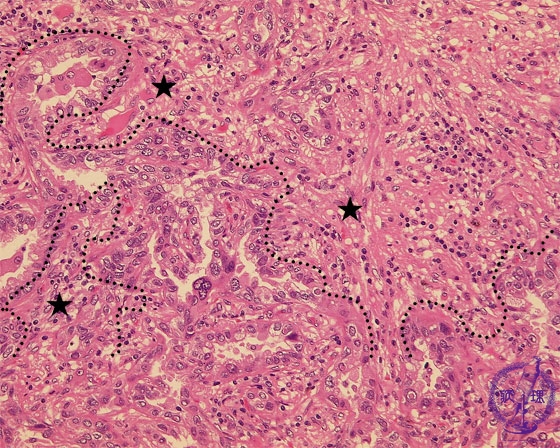

- ★(17)Non-small cell lung carcinoma(adenocarcinoma)

Microscopic view (HE stain, high power view): Adenocarcinoma of lung. Centrally within the carcinoma, tumor cells form irregular tubules and proliferate by invasion. There is a predominantly lymphocytic infiltrate within the complex, intricate stroma.